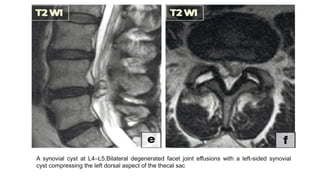

A synovial cyst at L4–L5.Bilateral degenerated facet joint effusions with a left-sided synovial

cyst compressing the left dorsal aspect of the thecal sac

A synovial cystat L4–L5.Bilateral degenerated facet joint effusions with a left-sided synovial cyst compressing the left dorsal aspect of the thecal sac